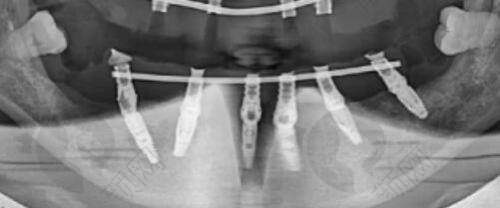

隆鼻是医美整形中较为热门的项目。人民解放军第458医院提供多种隆鼻方式,以下是人民解放军第458医院2025年隆鼻项目价格表:

| 整形项目 | 价格参考 |

|---|---|

| 鼻中隔软骨隆鼻 | 16760 - 55627 |

| 玻尿酸隆鼻 | 24234 - 68593 |

| 硅胶隆鼻 | 16137 - 53274 |

| 假体隆鼻 | 17107 - 56586 |

| 胶原蛋白隆鼻 | 16795 - 65569 |

| 隆鼻失败修复 | 37853 - 82865 |

| 膨体隆鼻 | 24293 - 68287 |

| 自体耳软骨隆鼻 | 17003 - 57637 |

| 自体肋软骨隆鼻 | 16144 - 55655 |

| 自体脂肪隆鼻 | 24784 - 69004 |

| 耳软骨隆鼻 | 24407 - 71697 |

| 隆鼻价格 | 24465 - 70087 |

| 软肋骨隆鼻 | 24227 - 71862 |

| 隆鼻手术 | 24585 - 75593 |

| 假体隆鼻 | 24086 - 77998 |

| 隆鼻假体取出 | 24907 - 80007 |

| 隆鼻价目表 | 24344 - 74968 |

需要注意的是,以上价格仅供参考,实际价格请到医院面诊获取。不同的隆鼻方式有其各自的特点和适用人群,患者可以根据自己的需求和医生的建议来选择合适的隆鼻方法。